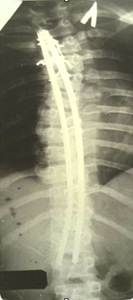

Л.Л. Роднянский предложил для коррекции сколиотической деформации одно-пластинчатый эндокорректор. Методику характеризовала малая травматичность и безопасность оперативного вмешательства. Однако, недостаточная жесткость конструкции, малое число блоков крепления корректора не позволяли оперировать тяжелые формы деформации. В случаях вмешательства у пациентов с начальной стадией заболевания, с деформацией I-II степени не удавалось избежать прогрессирования искривления. В послеоперационном периоде происходила достаточно быстрая потеря коррекции и в общем она составляла приблизительно 40%. Кроме этого достоверно нарастала ротационная деформация позвоночника на вершине искривления.

Различные варианты однопластинчатого эндокорректора